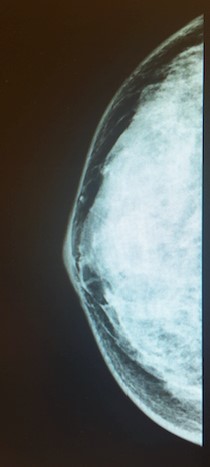

Laporan Kepadatan Payudara dan Mamografi

Wanita muda dan wanita dari etnis Asia diketahui memiliki payudara yang padat.

Kepadatan payudara disebabkan oleh payudara yang memiliki lebih banyak jaringan berserat dan kelenjar dan lebih sedikit jaringan lemak di payudara.

Payudara padat - lebih "putih"

Payudara berlemak - lebih "hitam" pada MMG